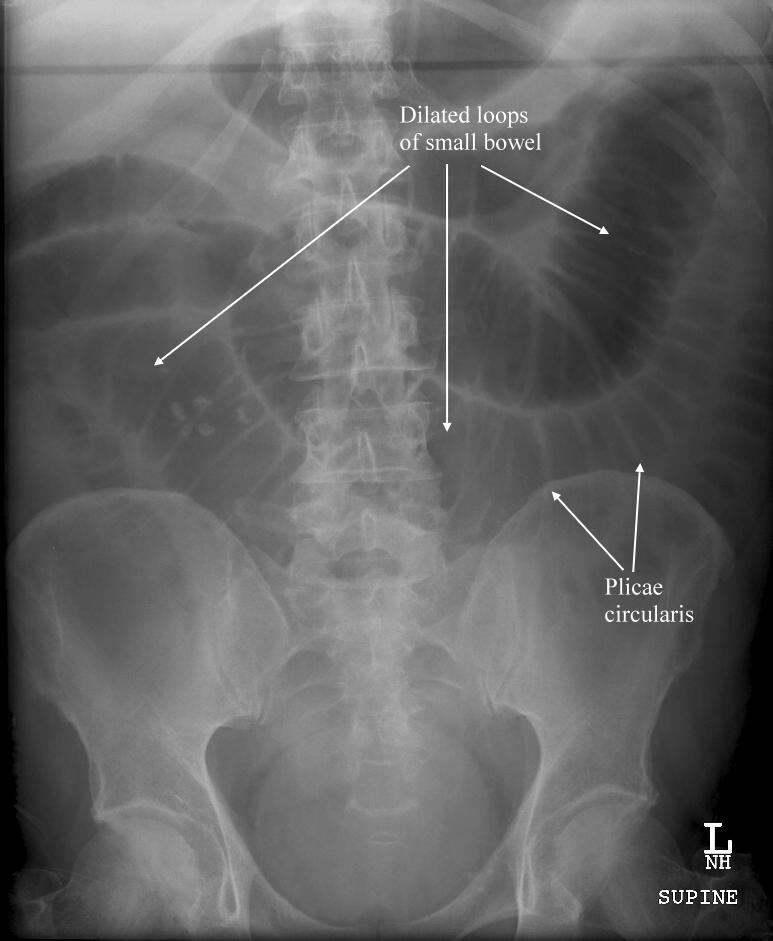

Mechanical small bowel obstruction related to abdominal masses, recommend additional follow-up or biopsy.